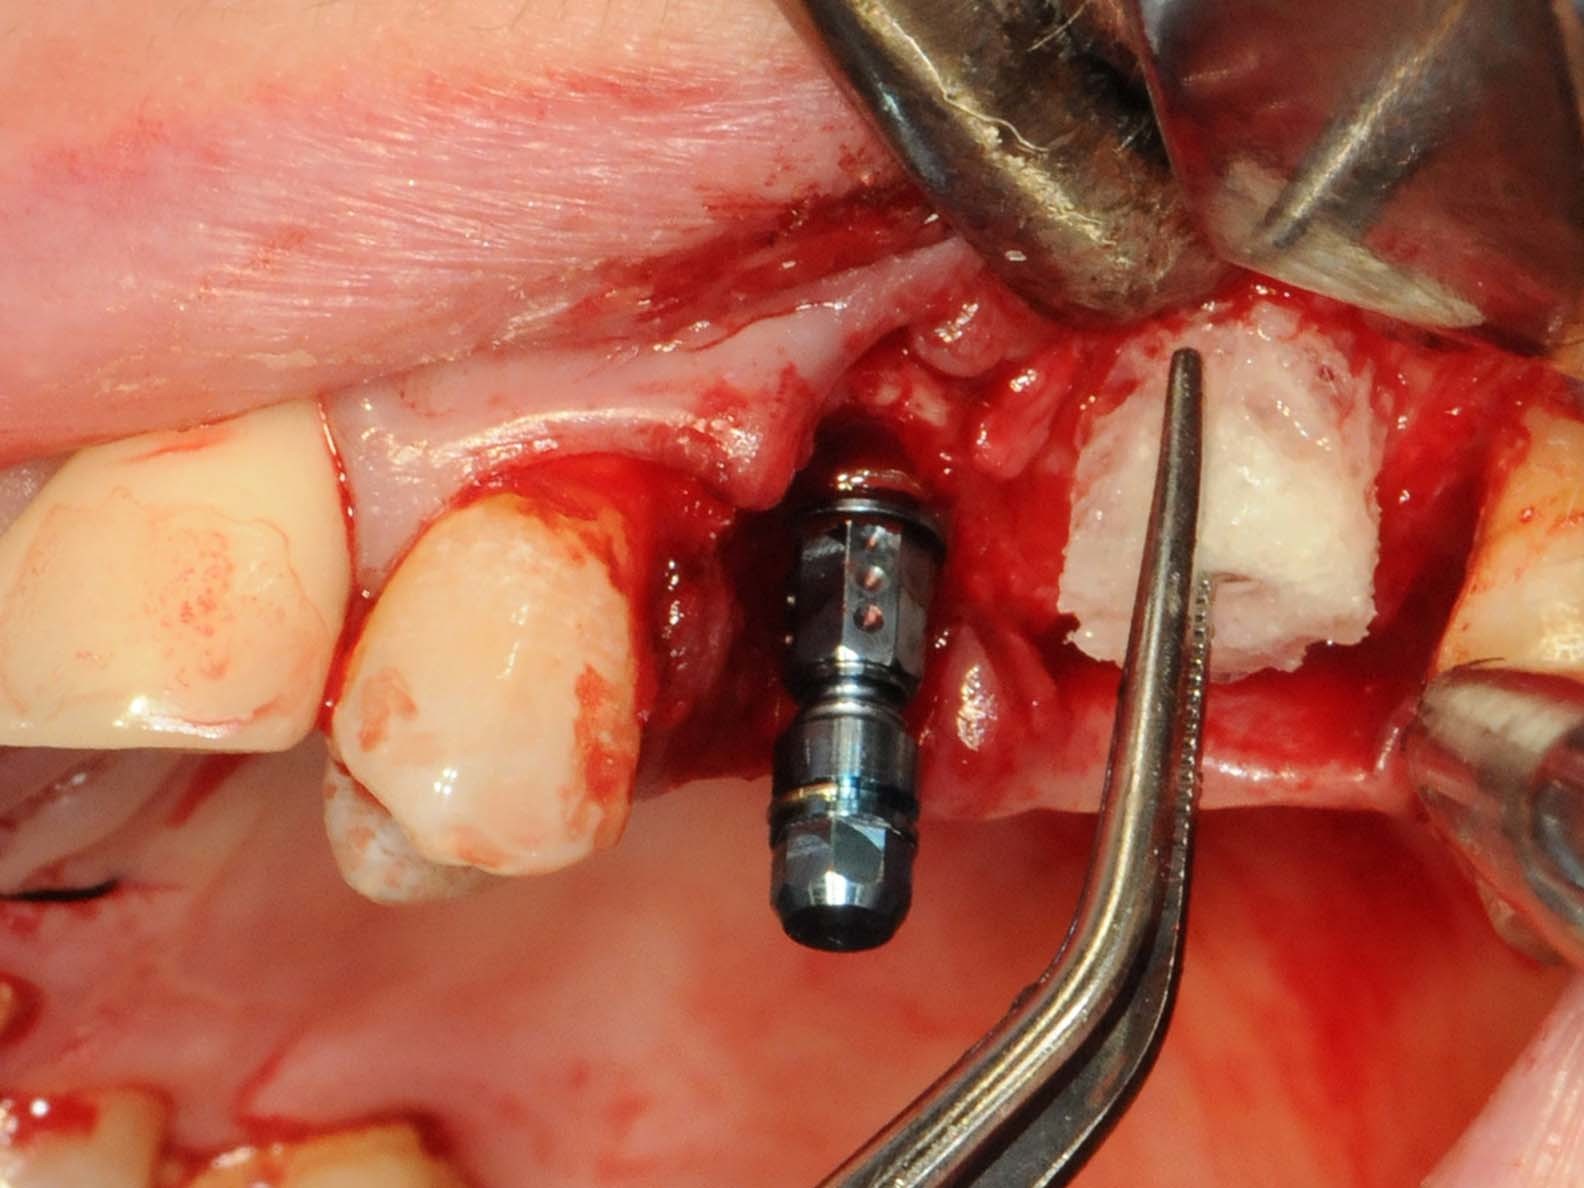

Abb 11 Straumann® PURE Ceramic Implantat in situ

Abb. 11: Straumann® PURE Ceramic Implantat in situ

Unter oraler Antibiose mittels Clindamycin 600mg 2 x/Tag erfolgte zunächst die typische minimalinvasive Präparation des Mukoperiostlappens unter Erhalt der Papillen zu den Nachbarzähnen in Regio 12 (Abb. 6), nachdem die Brücke von Zahn 11 nach 14 entfernt wurde (Abb. 7). Wegen Nichtanlage von 13 steht der Zahn 14 in dessen Region. Seinerzeit wurde der Zahn 14 zur Aufnahme einer entsprechenden Eckzahnkrone umgestaltet. Die Implantatbettpräparation (Abb. 8 und 9) für das Straumann PURE Ceramic Implantat (Ø 3,3 mm, Länge 12mm) erfolgte gemäß dem Straumann Guided Surgery Protokoll. Die abschließende Implantatinsertion wurde dem Protokoll für die Straumann PURE Ceramic Implantatlinie gemäß durchgeführt (Abb. 10 und 11). In der Implantatsetzungsregion des zweiten Quadranten wurde zunächst die Inlay-Brücke von Zahn 25 nach 27 entfernt. Seitens des zahntechnischen Labors wurde das Zahninlay von Zahn 27 von der Brücke getrennt und wieder inkorporiert. Nach der Extraktion des tief zerstörten Zahnes 25 erfolgte die typische Mukoperiostlappenpräparation. Nach Darstellung des Insertionssitus kam die massive vestibuläre Knochendefizitsituation in Regio 26 zur Darstellung (Abb. 12). Zunächst wurde die Präparation der Implantatstollen in Regio 25 und 26 gemäß dem Straumann Guided Surgery-Protokoll durchgeführt. In Regio 25 wurde ein Straumann Bone Level Roxolid Implantat (Ø 4,1 mm, Länge 12mm) als Sofortimplantation eingesetzt (Abb. 13 und 14). In Regio 26 wurde ein Knochenring CHB¹⁶ zur Augmentation des vestibulären Knochendefizits entsprechend des ossären Knochenabhanges angeschrägt und in der Höhe eingekürzt (Abb. 15). Die Anpassung des homologen Ringes erfolgt unter Fixierung mit der bonering fix-Zange und Anwendung einer 10-mm-Diamanttrennscheibe (Abb. 16).